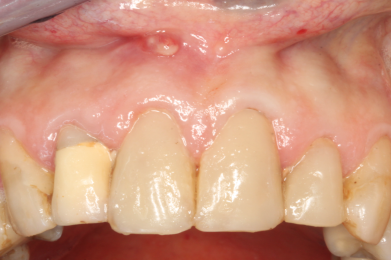

- Defekte oder braune, schwarze Stellen an den Zähnen, Kronen oder Brücken / Verweigerung von Essen wegen Heiß-/Kaltempfindlichkeit oder Empfindlichkeit süß-sauer / „Fährt rein!“

- Gerötetes oder "zurückgegangenes" Zahnfleisch / Essen hängt ständig zwischen den Zähnen

- Zahnfleisch sieht entzündet (gerötet) aus / ggf. fällt Mundgeruch auf